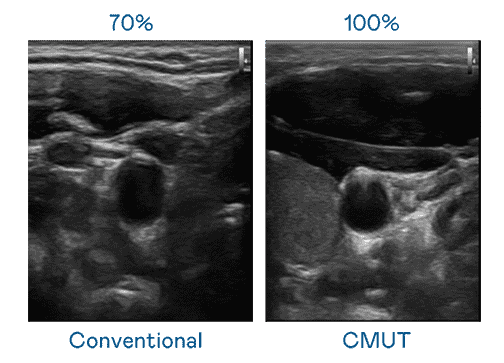

CMUT 技术是一种用电容式微机电元件来产生超音波讯号的技术。。。与传统 PZT 压电式技术相比,,,CMUT 频宽增加 30%,,更宽频的超音波讯号让影像解析度大幅提升,,是实现高影像品质医疗超音波扫描、、促进精准医疗发展的关键技术。。。。

大频宽带来超清晰影像

超音波影像的解析度高低,,首先取决于探头能发出的讯号频宽。。菠菜论坛 CMUT 可提供高清晰的超音波讯号,,,提供高频宽、、、、高灵敏度、、、影像纹理细节更高的超音波影像,,,,协助医护人员缩短影像判读时间及利用精准的医疗影像进行诊断。。。。